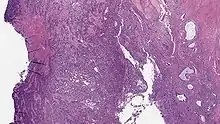

| Micrograph of a low-grade endometrial stromal sarcoma. H&E stain. | |

Low-grade endometrial stromal sarcoma consists of cells resembling normal proliferative phase endometrium, but with infiltration or vascular invasion. These behave less[3] aggressively, sometimes metastasizing, with cancer stage the best predictor of survival. The cells express estrogen/progesterone-receptors.